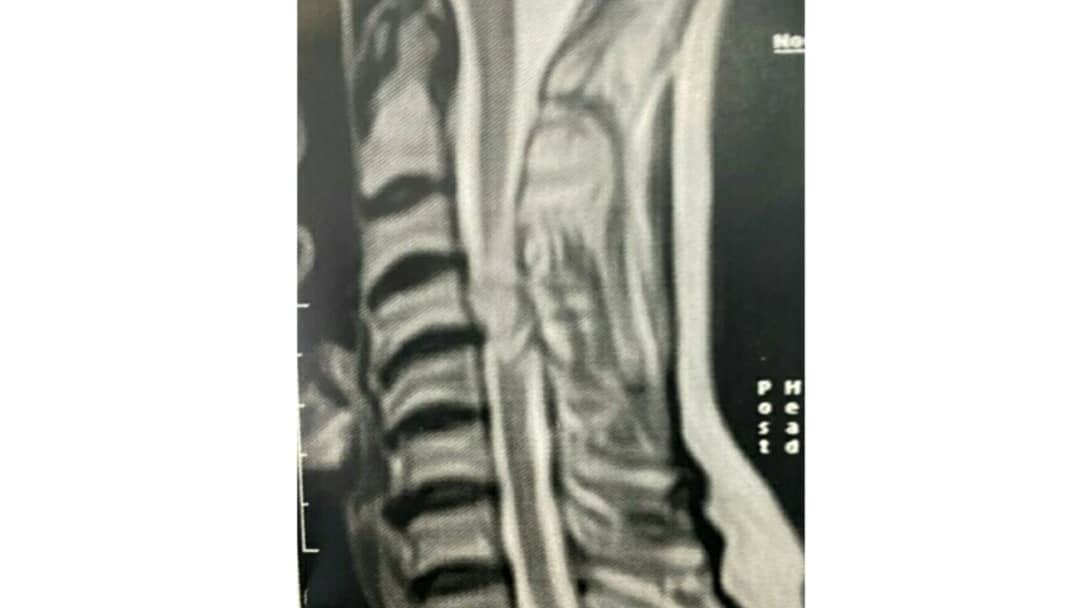

بیمار خانم سالخورده که با درد گردن ضعف و لاغری عضلات کف دست راست مراجعه کرده بودند

تشخیص: مننژیومای سرویکال

تومور خوش خیم نخاع گردن

عمل جراحی میکروسکوپیک تحت نورومانیتورینگ دائمی حین عمل

تصاویر قبل از عمل